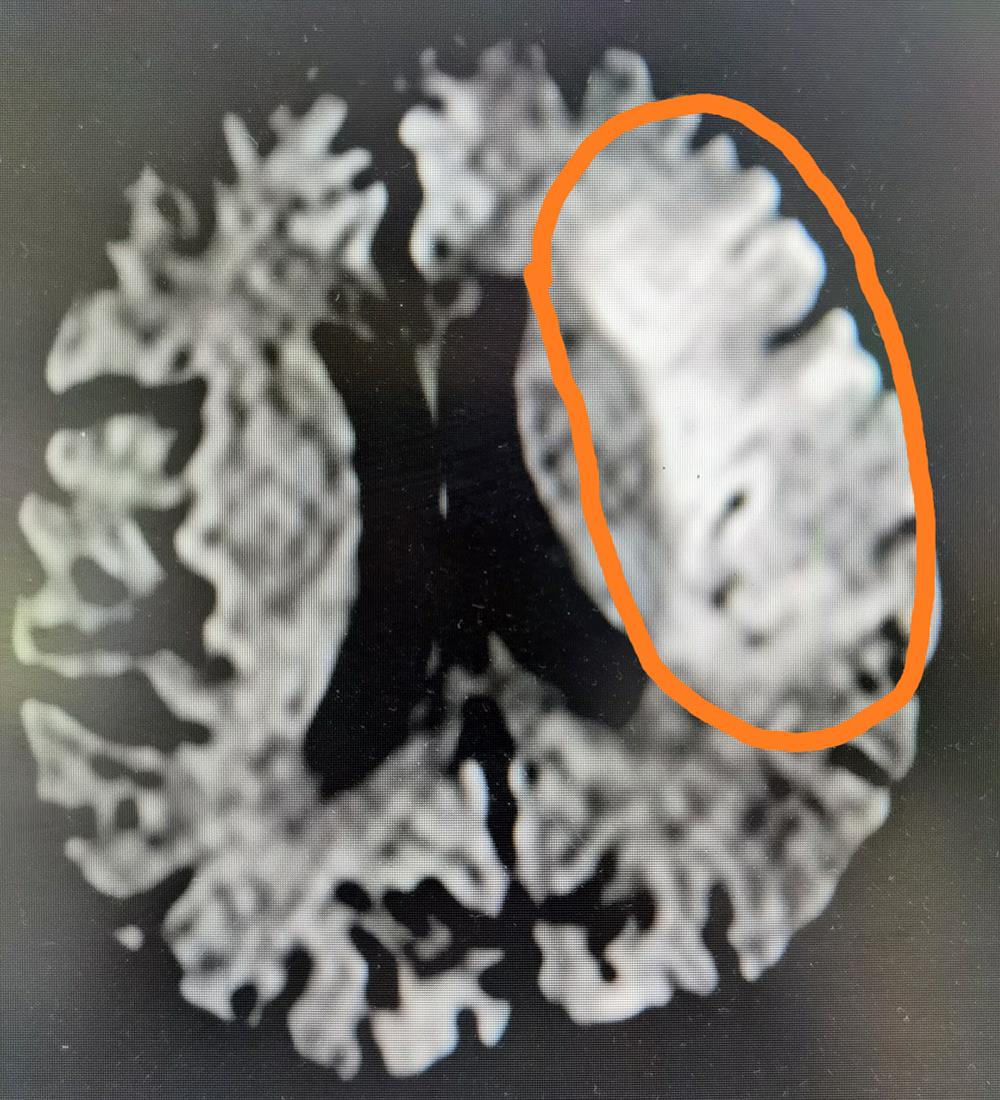

今年54岁的男性患者因突发意识不清、烦躁、完全不能言语、右侧肢体偏瘫,被工友发现后紧急从单位送来榆林二院求诊。在卒中中心诊查后急行头颅影像检查,发现该患者左侧大面积脑梗死,右侧大面积脑软化灶,因其意识不清,烦躁,核磁血管检查不能配合,紧急收住脑科医院神经内科一病区进行救治。